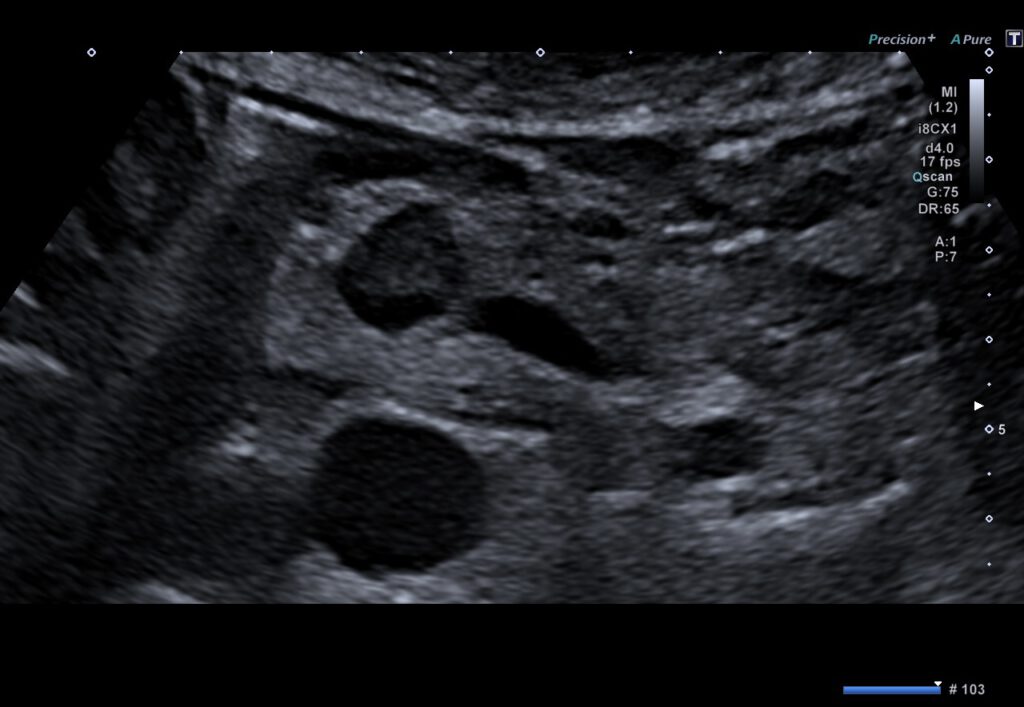

92-jährige Patientin mit Insulinom des Pankreas.

Wegen rezidivierender Hypoglykämien erfolgte die stationäre Behandlung. In der Abdomensonographie wurde ein kleiner echoarmer Tumor im Bereich des Pankreaskopfes auffällig, weswegen anschließend eine Endosonographie durchgeführt wurde. Hierbei bestätigte sich das Vorliegen eines hypervaskularisierten Tumors am Übergang zwischen Pankreaskopf und -korpus. Bei Multimorbidität und hohem Patientenalter wurde sich gemeinsam für die minimalinvasive Therapie der endosonographisch-geführten Ethanolinjektion entschieden. Nach Applikation von 1,5 ml 96% Ethanol stellte sich die Raumforderung in der kontrastmittelgestützten Sonographie-Kontrolle avital dar. Der Blutzuckerspiegel normalisierte sich rasch, die Patienten wurde ohne Notwendigkeit einer medikamentösen Therapie entlassen.